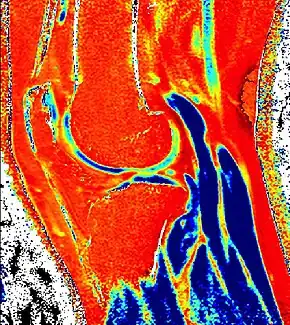

dGEMRIC T1 Map of knee cartilage

Purposemeasures relative proteoglycan content of articular cartilage